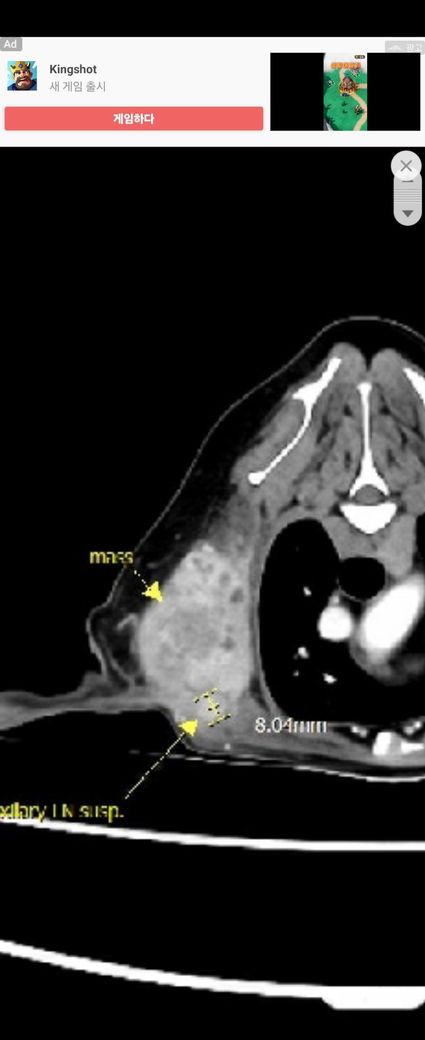

강아지 세포검사 칼시노마, 조직검사 침윤성지방종이래요

부위는 겨드랑이 윗부분,

의사한분은 양성일거다

한분은 악성인데 조직검사가 잘못된것같다.

림프도 한분은 전이다

한분은 반응성이다

폐에 결절도 한분은 전이다

한분은 노령성이다.

검사전부터 염증이 심했고 조직검사후 항생제 복용후 염증은 좀 가라앉은 상태예요